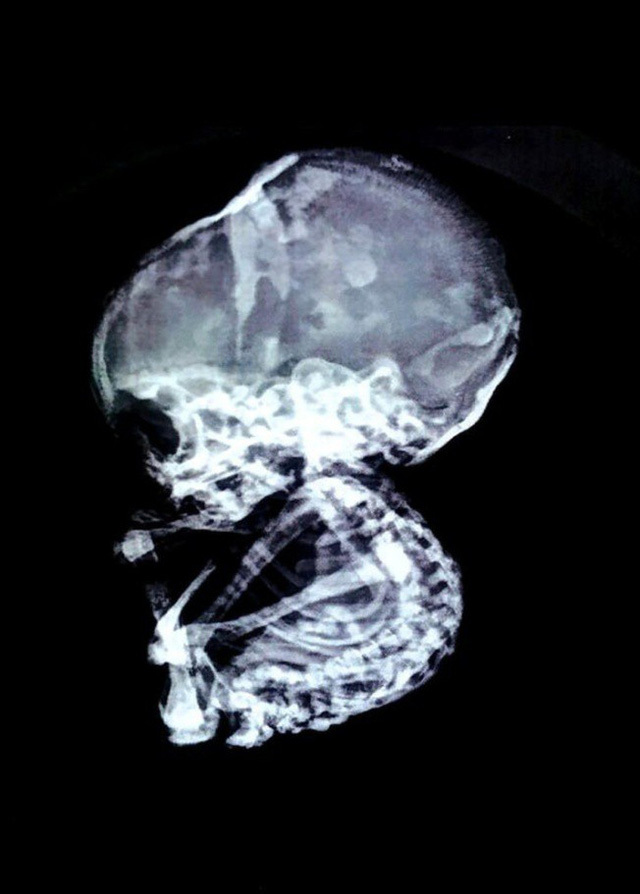

“Chụp chiếu cho thấy đường ruột cô ấy bị tắc nghẽn nghiêm trọng. Ống dẫn thức ăn bị một vật có cấu trúc giống như đá chèn ép. Thông thường bào thai chết lưu sẽ bị thối, có thể gây nhiễm trùng cho cơ thể người mẹ nhưng trong trường hợp này, thai nhi đã tự ướp xác, tích tụ muối và hóa đá”, tiến sĩ Nilesh Junankar chia sẻ.

Vị bác sĩ phẫu thuật nội soi cũng cho biết các trường hợp bào thai hóa đá là vô cùng hiếm gặp, chỉ có khoảng 300 trường hợp được ghi chép trong lịch sử. Những trẻ sơ sinh hóa đá thường là kết quả của việc mang thai ngoài tử cung và không có cách nào rời khỏi cơ thể người mẹ.

| Thai nhi hóa đá khi 4 tháng tuổi và đã phát triển tương đối đầy đủ trong bụng mẹ |